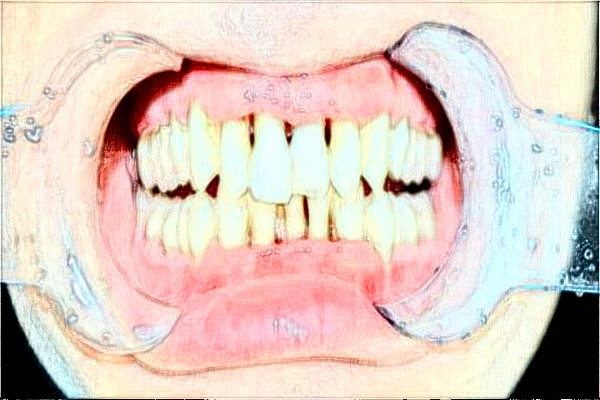

2024中山大學附屬第五醫(yī)院補牙案例

不知道是什么原因造成的,前段時間忽然就有了牙痛的現(xiàn)象,當時特別疼痛,吃了很多止痛的藥物,可是并沒有緩解,于是就來到中山大學附屬第五醫(yī)院口腔科找了一位醫(yī)生咨詢,醫(yī)生是出現(xiàn)了蛀牙的現(xiàn)象,需要補牙,這顆牙齒在里邊,醫(yī)生建議我用銀汞合金,醫(yī)生說這種補牙的材料雖然顏色不漂亮,但是耐磨性比較好,而且價格也比較便宜,然后醫(yī)生就對我的蛀牙部位進行了清潔以及消毒,用專業(yè)的材料補了這顆牙齒,如今很長時間過去了,這個牙齒使用起來的時候很舒適。